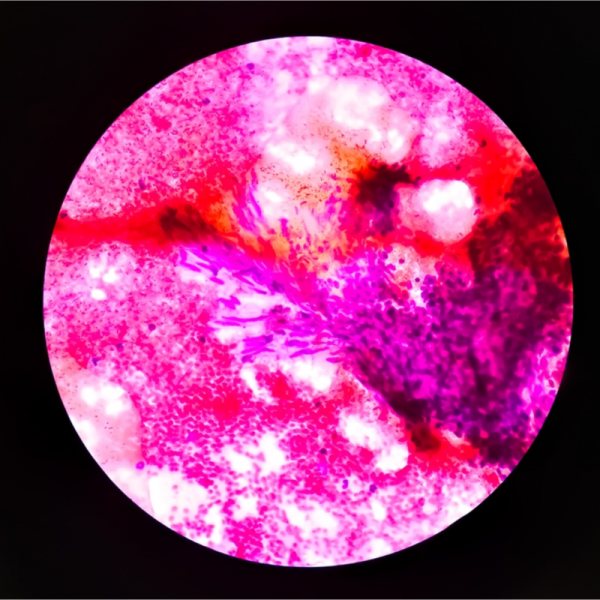

Die Diagnose eines Adenoms kann je nach Art der Erkrankung im Rahmen einer Routineuntersuchung, bzw. Frühdiagnoseuntersuchung diagnostiziert werden. Hierzu gehört beispielsweise das Adenom des Magen-Darm-Trakts, welches durch eine Darmspiegelung und eine anschließende mikroskopische Untersuchung festgestellt wird. Die Diagnosestellung eines Fibroadenoms erfolgt hingegen durch eine Ultraschalluntersuchung (Sonografie) oder eine Punktion.